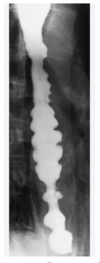

What dx? What is the first line tx of choice? What dx test?

esophageal spasm CCB then move on to TCA if CCB does not work esophageal mamometry